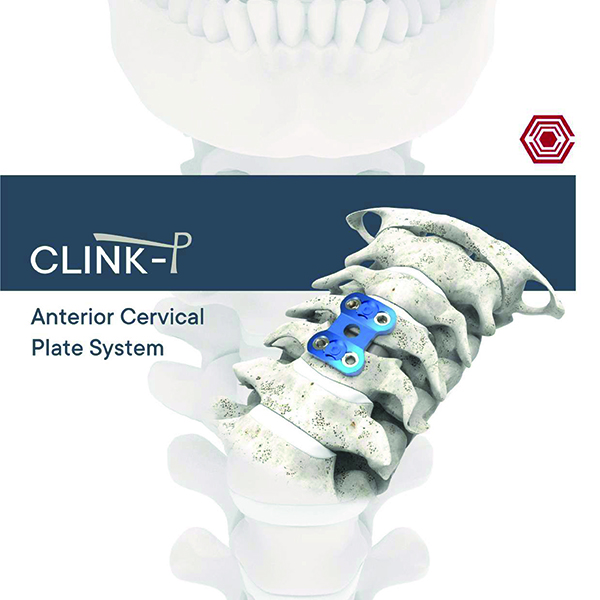

Clink - P

Akif Kaya Aybek

Norm Akademi

- Surgical Technique

- Implant Types

- Instrument Container

- Instrument Types